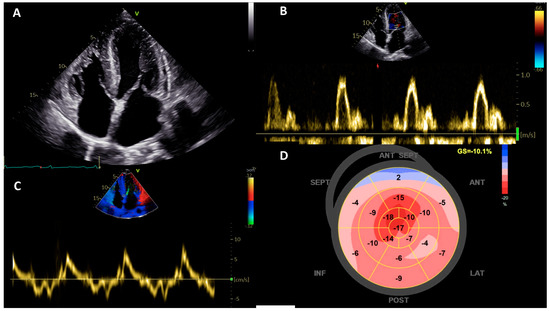

| Cardiac amyloidosis | 2D: Concentric LVH with preserved LVEF and progressive reduction in LV volumes; biventricular involvement; early diastolic dysfunction with biatrial enlargement; pericardial effusion. Strain imaging: Relative apical sparing pattern with increased EFSR; reduced GCW and GWE by LVMWI. | Extracardiac involvement: neurological (peripheral neuropathy, carpal tunnel syndrome, autonomic neuropathy, spinal cord stenosis), ocular (vitreous opacity, cataract) ECG: voltage discordance pattern (increased LV mass at cardiovascular imaging with normal or reduced QRS voltages); pseudoinfarction pattern; AF; conduction abnormalities. |